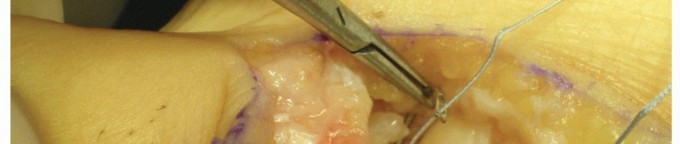

If a longitudinal tear of the plantar plate is detected (grade 3 T- or 7-shaped lesion), it can be repaired through interrupted nonabsorbable 3.0 sutures placed with the help of a small needle holder (TECH FIG 2).

- TECH FIG 2 • Suturing a longitudinal tear of the plantar plate.